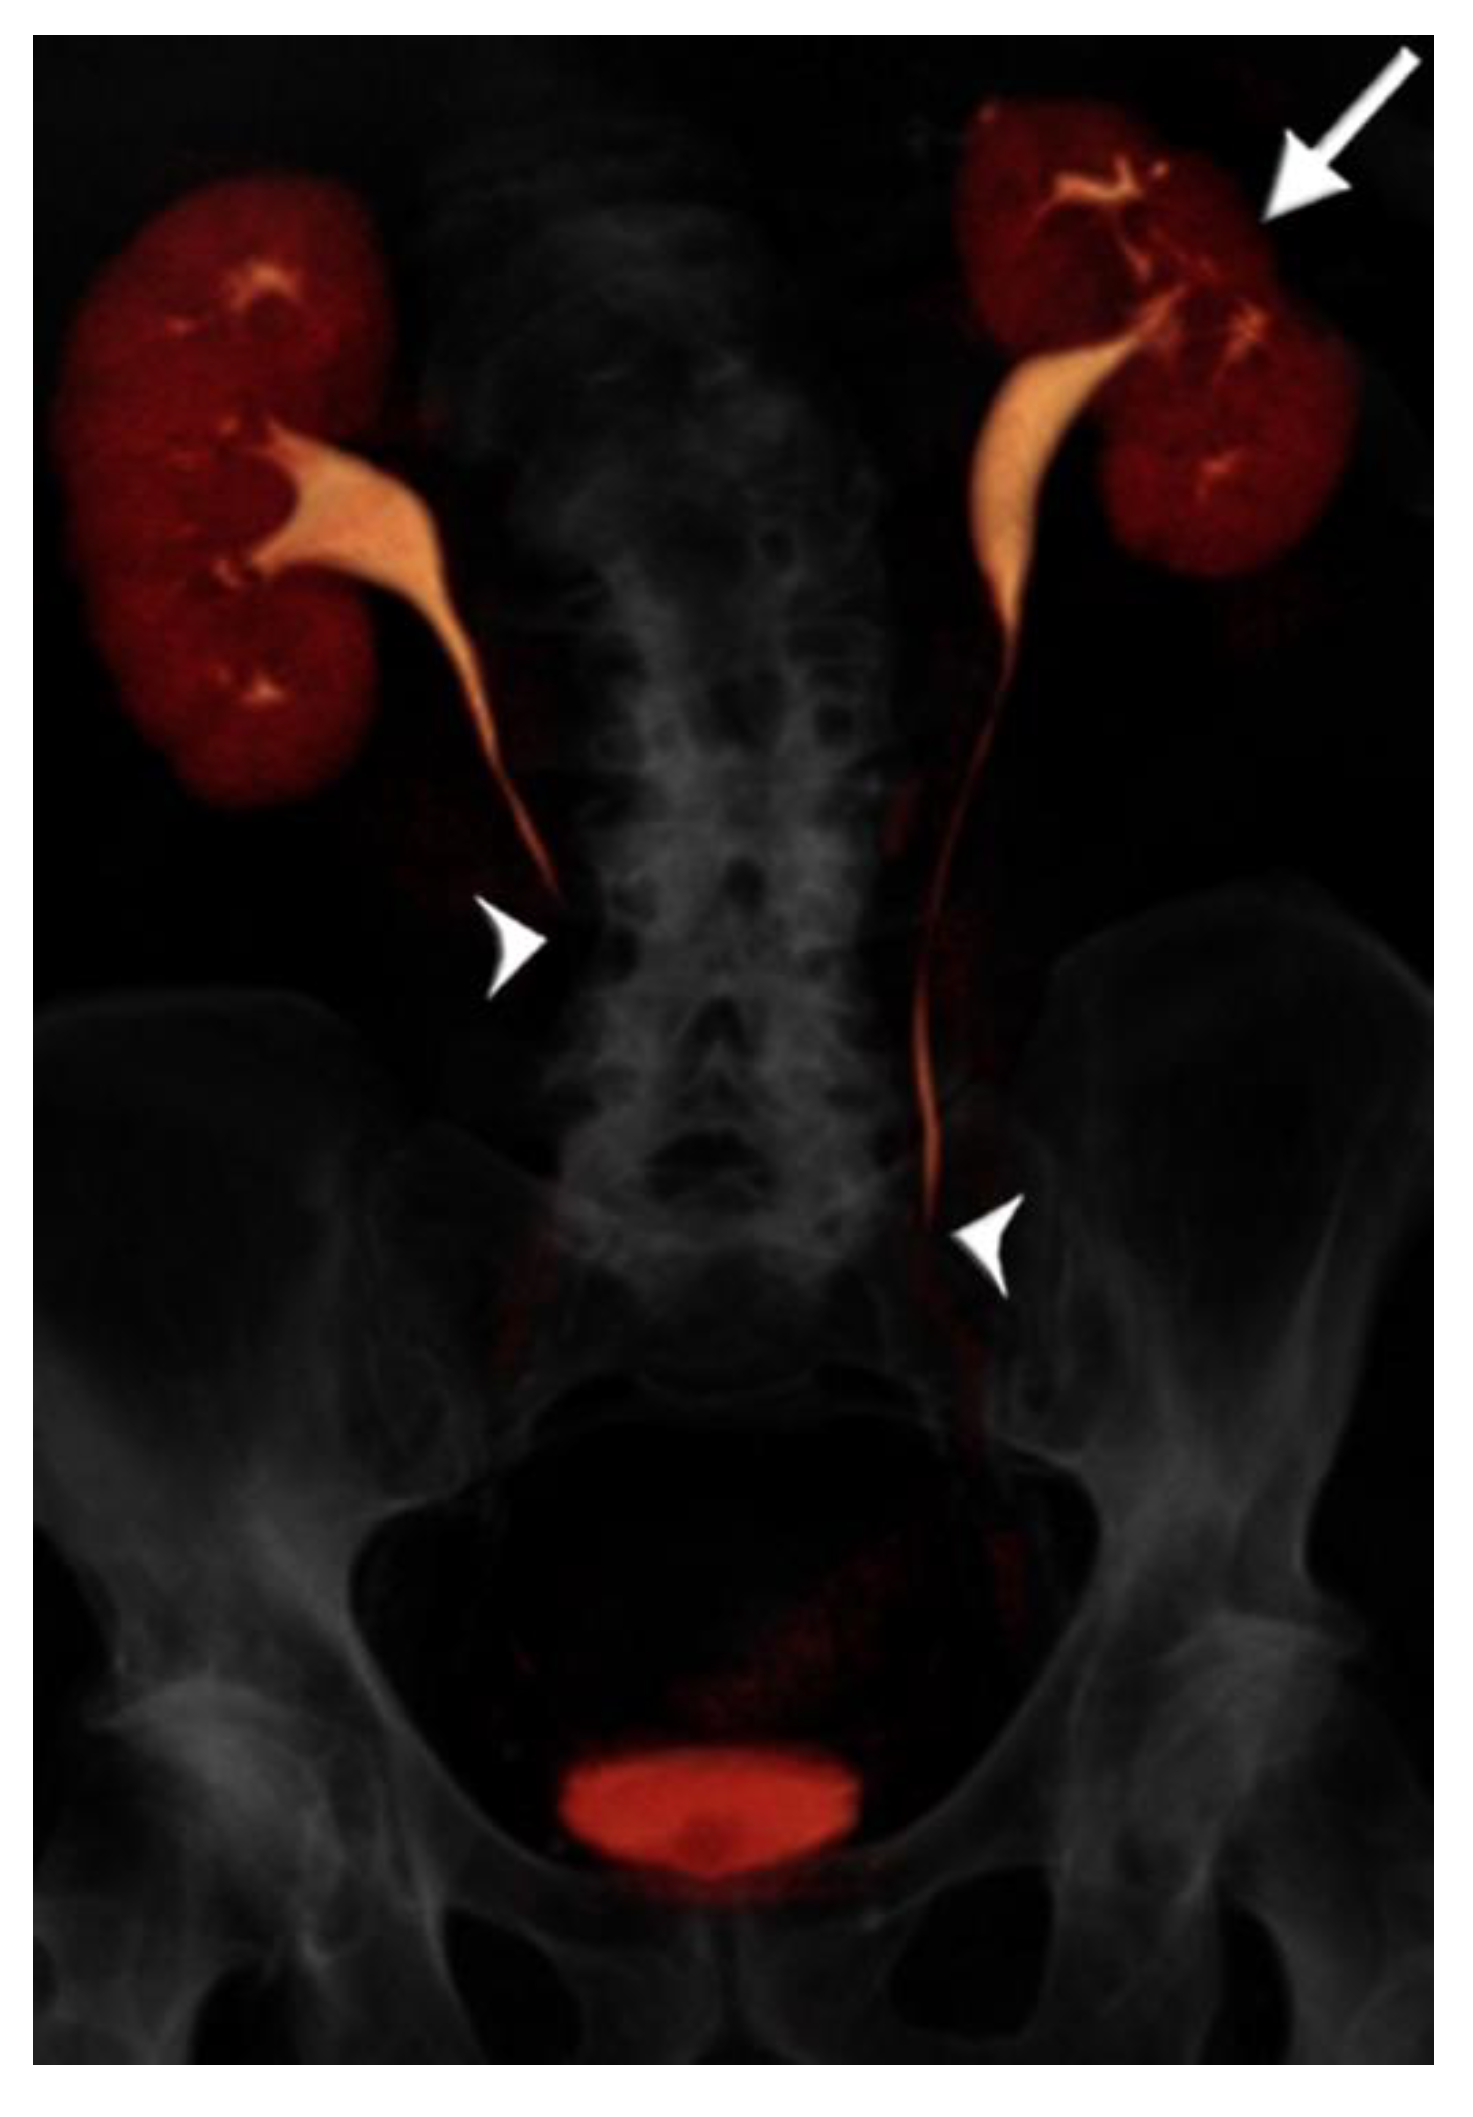

2.2. CT Urography Technique

- Cheng, K.; Cassidy, F.; Aganovic, L.; Taddonio, M.; Vahdat, N. CT urography: How to optimize the technique. Abdom. Radiol. 2019, 44, 3786–3799. [Google Scholar] [CrossRef]